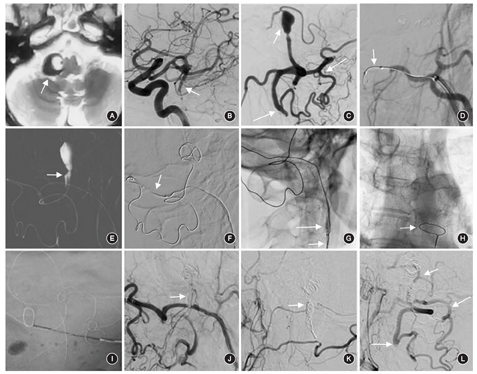

患者男,65岁,因"双眼视物模糊半年,加重1周"为主诉入院。外院行MRI可见右侧延髓旁血管流空影,考虑为椎动脉动脉瘤(图1A)。此次入院后行全脑DSA显示,双侧椎动脉自起始段闭塞,V3段至椎动脉颅内段由双侧颈外动脉通过枕动脉代偿供血而显影,右侧椎动脉V4段可见一梭形动脉瘤,最大直径为14.3 mm,远端1 mm处可见椎动脉分支—小脑后下动脉(PICA)发出,其以远的椎动脉未见显影(图1B,图1C)。手术操作包括:(1)球囊闭塞试验:患者取仰卧位,在局部麻醉下行右侧股动脉穿刺,置入8F股动脉鞘,在泥鳅导丝的配合下同轴引入8F MPA指引导管(美国强生公司),头端置于右侧颈总动脉近分叉处,沿8F指引导管引入5F Navien导管(115 cm,美国美敦力公司),头端超选至右侧枕动脉上升段的末端,行DSA进一步明确动脉瘤的解剖结构。在10系ASAHI微导丝的配合下引入高顺应性球囊(HyperForm,3 mm×7 mm,美国美敦力公司),缓慢给予压力充盈,DSA提示右侧枕动脉的血流完全阻断,球囊以远的枕动脉及代偿的椎动脉、动脉瘤均未见显影(图1D),持续闭塞35 min,观察患者无头晕、呼吸困难、肢体运动、感觉及言语障碍等脑缺血相关症状后,撤出球囊。(2)颅内动脉瘤的栓塞:患者予全身麻醉,在工作角度路图下,微导丝配合Headway Duo微导管(156 cm,美国Microvention公司)超选至迂曲的吻合支,头端置于右侧椎动脉V4段动脉瘤的近端(图1E),撤出微导丝,引入首枚Axium弹簧圈(14 mm×30 cm,美国美敦力公司),待填塞入动脉瘤瘤腔约1/2长度的弹簧圈时,因弹簧圈的推送困难,遂撤出更换为MicroPlex弹簧圈(8 mm×20 cm,美国Microvention公司),同样在填塞约弹簧圈的1/2长度时无法继续推送,多次尝试失败后,缓慢回撤推送杆使弹簧圈末端自动解脱。然后继续将弹簧圈推送杆进一步向前推送时,发现弹簧圈的中间部分解旋。(3)弹簧圈解旋的处理:①首先尝试缓慢回撤微导管,发现部分填塞的弹簧圈自动脉瘤瘤腔退出,然后采用14系微导丝经微导管内向前推送弹簧圈末端,同样推送困难,效果不佳。②在微导丝的配合下,沿5F Navien导管引入SV球囊(3 mm×15 mm,美国波士顿科学公司)至中间导管的头端(图1F),缓慢充盈球囊使其紧贴支撑导管的内壁。通过球囊-Headway Duo微导管-Navien支撑导管三者之间的相互作用力,缓慢回撤整个系统,通过DSA可观察到弹簧圈随上述系统向近端移动(图1G)。完全撤出中间导管、微导管,可见弹簧圈尾端滞留于右侧颈总动脉内。③沿8F指引导管引入直径为10 mm的鹅颈抓捕器(美国美敦力公司),头端至目标位置后,打开抓捕器,旋转并套取解旋的弹簧圈,将8F指引导管前推,收紧抓捕器,抓取成功后,将弹簧圈完全撤出(图1H,图1I)。④在微导丝的配合下引入另一根Headway Duo微导管,再次通过迂曲的吻合支,头端置于右侧椎动脉V4段的动脉瘤瘤腔内,引入Axium弹簧圈(9 mm×30 cm,美国美敦力公司),填塞部分后依然推送困难,遂缓慢继续填塞,然后引入规格为8 mm×30 cm的Axium弹簧圈,填塞过程中微导管头端明显后退,填塞接近尾端时发现弹簧圈自动解脱(第1枚弹簧圈主要分布于动脉瘤瘤腔,第2枚弹簧圈闭塞椎动脉V4段的近端)。行DSA可见载瘤血管的近端及动脉瘤完全不显影(图1J),对侧颈外动脉造影可见枕动脉-椎动脉代偿的PICA显影,术后患者无明显不适,5 d后出院。术后8个月复查DSA显示,动脉瘤和右侧椎动脉均未显影,可见对侧枕动脉通过吻合支代偿椎动脉(图1K,图1L)。

弹簧圈的解旋通常发生在调整或撤回放置不理想的弹簧圈时,弹簧圈与动脉瘤内已填充的弹簧圈或支架发生缠绕牵拉,导致弹簧圈内部的抗解旋丝断裂,进而引起弹簧圈被拉长,向近端或远端移位[5]。目前,针对介入材料断裂(导管、冠状动脉支架、弹簧圈等)异位栓塞的处理尚无统一的标准。外科切开取出的方法创伤较大,且可能会破坏既有的吻合支代偿。常用的血管内处理方法包括:(1)使用特殊形状的导丝、导管缠绕(如猪尾状结构)。(2)采用腔内抓捕器套取。(3)采用活检钳抓捕等。但对于管径狭窄且迂曲的颅内血管中弹簧圈的解旋逃逸,由于上述抓捕系统粗大,存在到位困难、打开困难、容易损伤血管壁等问题[6]。此外,Amuluru等[7]报道,在球囊辅助栓塞颈内动脉动脉瘤的过程中,弹簧圈逃逸至同侧的大脑中动脉M3段,使用取栓支架Solitaire FR成功抓取。He等[8]报道使用自制的简易微型抓捕系统(头端由环形的14系微导丝、17系微导管、4-0缝线组成)套取由颈内动脉眼动脉段逃逸至大脑中动脉的弹簧圈。但由于本组患者特殊的血管条件,即路径严重迂曲,上述两种方法均不适用。因此,本组尝试使用球囊挤压微导管,通过支撑导管、球囊夹取微导管和弹簧圈向近端移动,待解旋的弹簧圈回撤至粗大的颈总动脉时,使用鹅颈抓捕器进行套取,顺利完成手术。